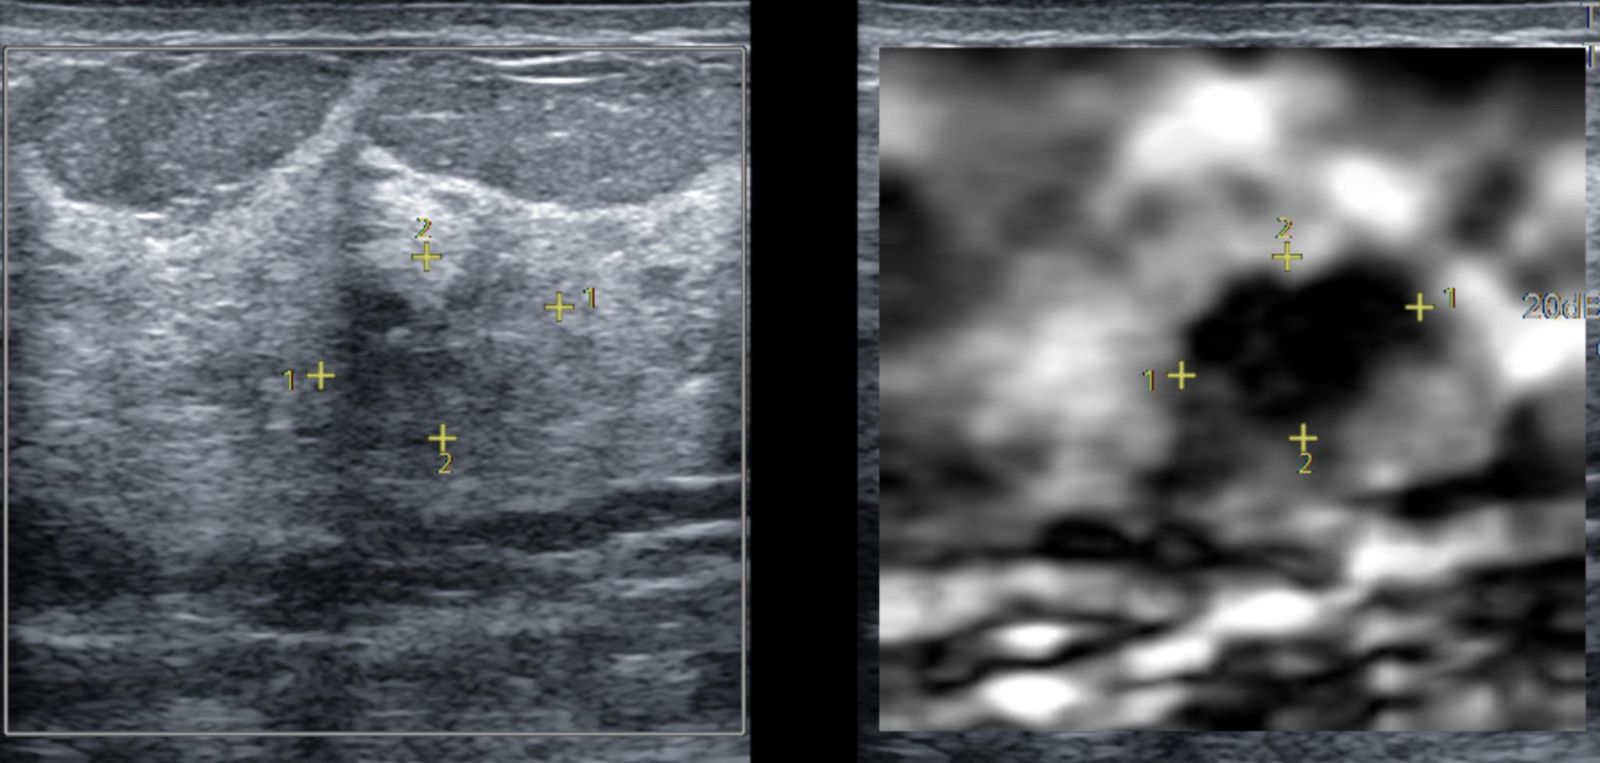

Trước khi quyết định phương pháp điều trị, bác sĩ sẽ dựa vào kết quả từ các xét nghiệm như siêu âm, chụp MRI, và sinh thiết (nếu cần thiết) để xác định xem khối u có phải là u lành tính hay ác tính.

Hút u chân không (VABB) thường được sử dụng khi có nghi ngờ về tính chất của khối u (như u xơ vú), giúp lấy mẫu mô để chẩn đoán. Nếu kết quả xác nhận u lành tính, bác sĩ có thể chỉ định điều trị bảo tồn, chẳng hạn như hút u chân không hoặc chỉ cần theo dõi định kỳ.